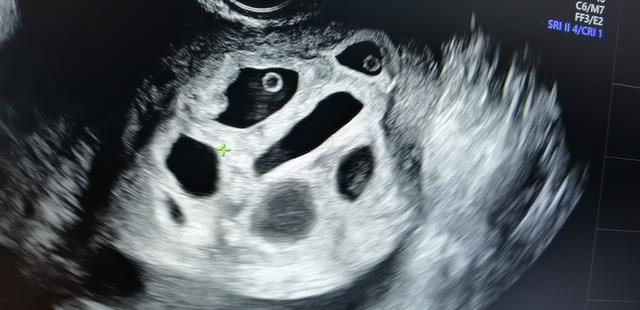

b超显示有8个孕囊。

上周来门诊基层促排卵。我怀了八胞胎。其中我们门诊检查说有5个有胎心率。结果,过了一天,他们去我们中心检查。我们看到有6个有胎心率,2个没有胎心率。在这种情况下,他们要么全部被棚掉,要么被缩小!最后还是比较顺利,保留了两个。胚芽的胎心率很好。